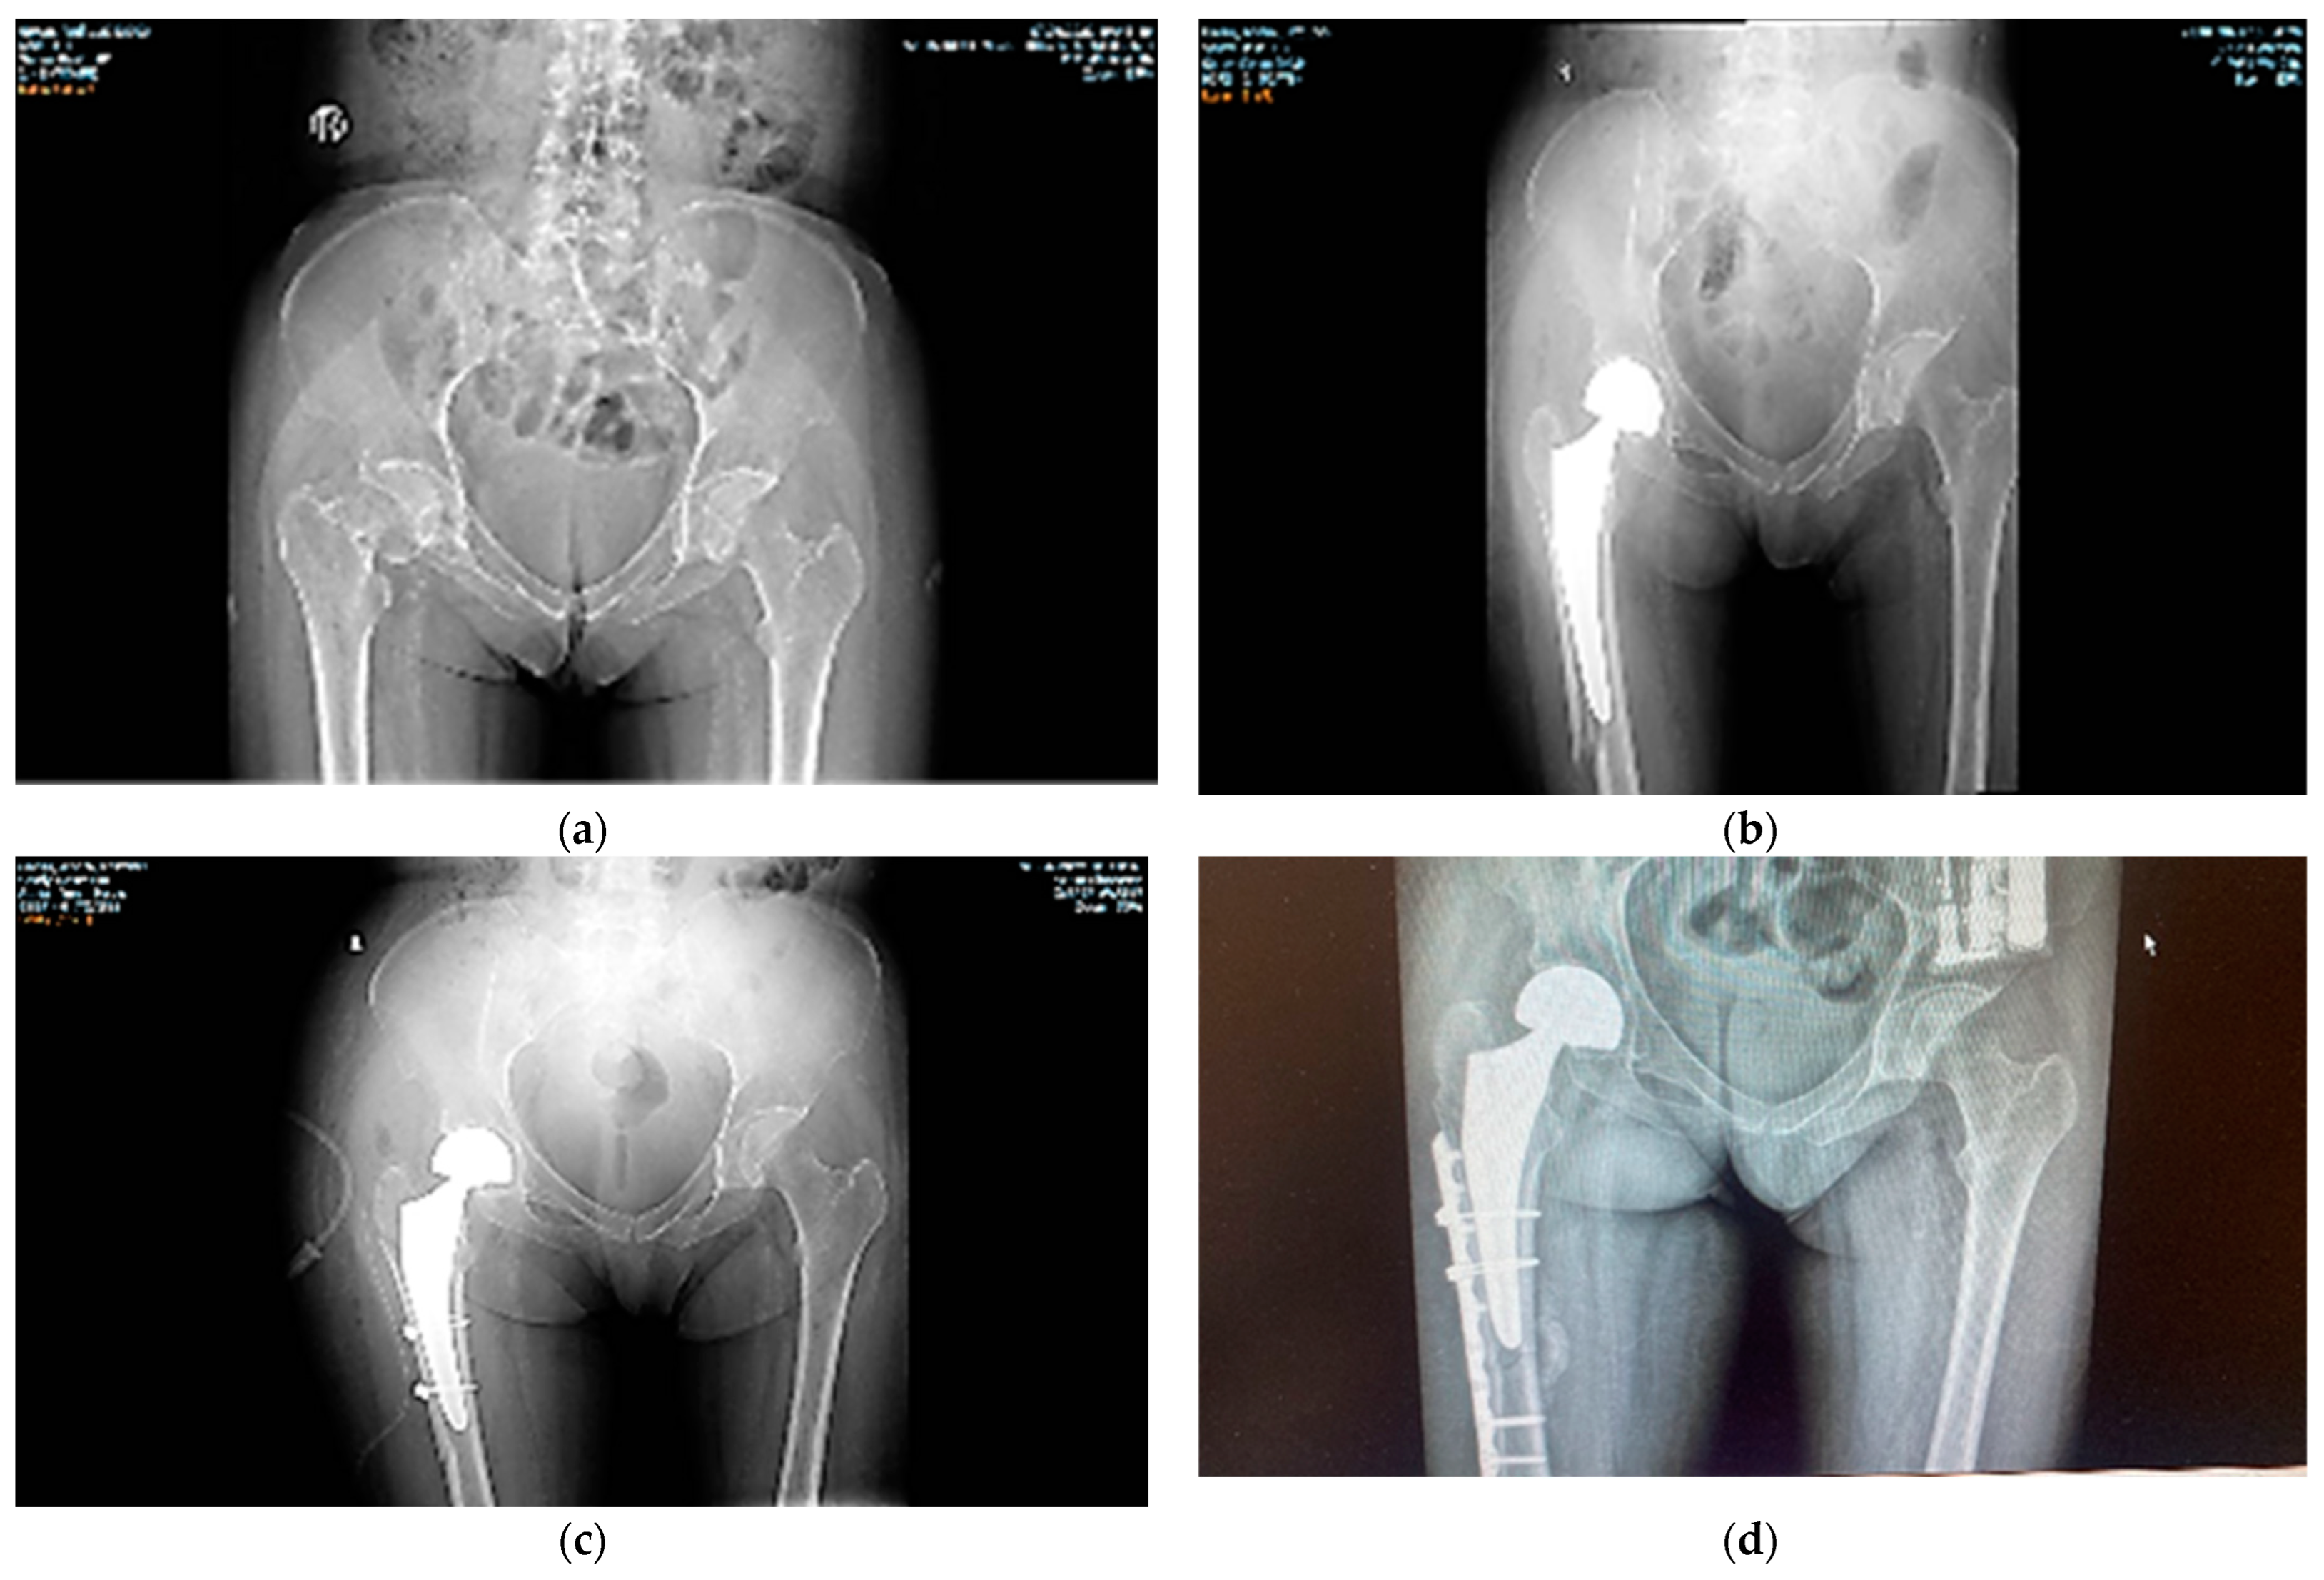

- surgery and appropriate manipulation and fixation of the bones, using the most suitable devices (screws, cables, cement/non-cement prostheses, etc.).